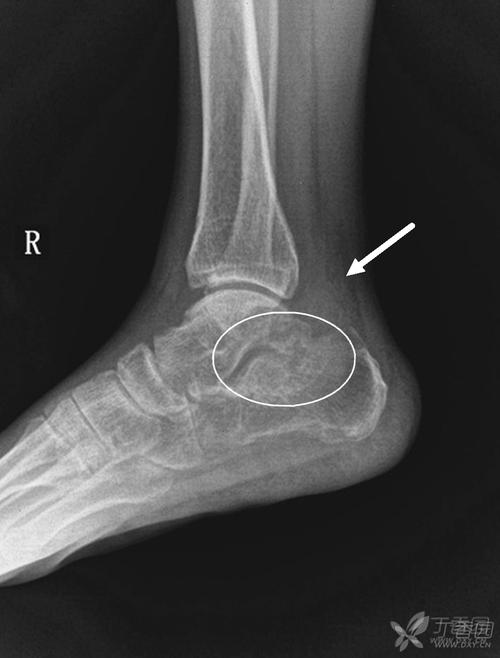

患者,男,17岁,扭伤致右踝关节肿痛活动受限3天.dr及ct如下

左脚脚踝一年前软骨骨折,没有发现,现在里面有一个类似于小骨片的东西